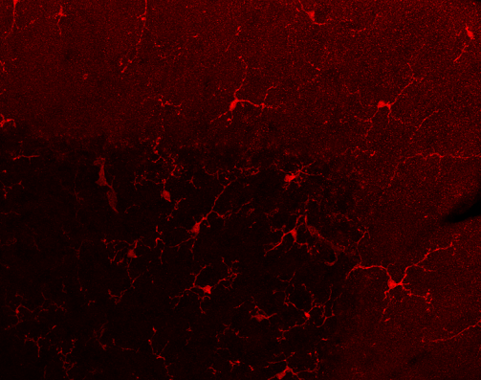

Descrito un efecto proinflamatorio de los endocannabinoides en el cerebro

Agencia SINC Un nuevo trabajo liderado por el Laboratorio de Neurofarmacología-NeuroPhar de la Universidad Pompeu Fabra (UPF) muestra en ratones que el aumento de endocannabinoides en el cerebro puede producir inflamación en áreas cerebrales concretas como el cerebelo, lo cual va asociado a problemas de coordinación motora fina. Los resultados son contrarios a lo que se […]